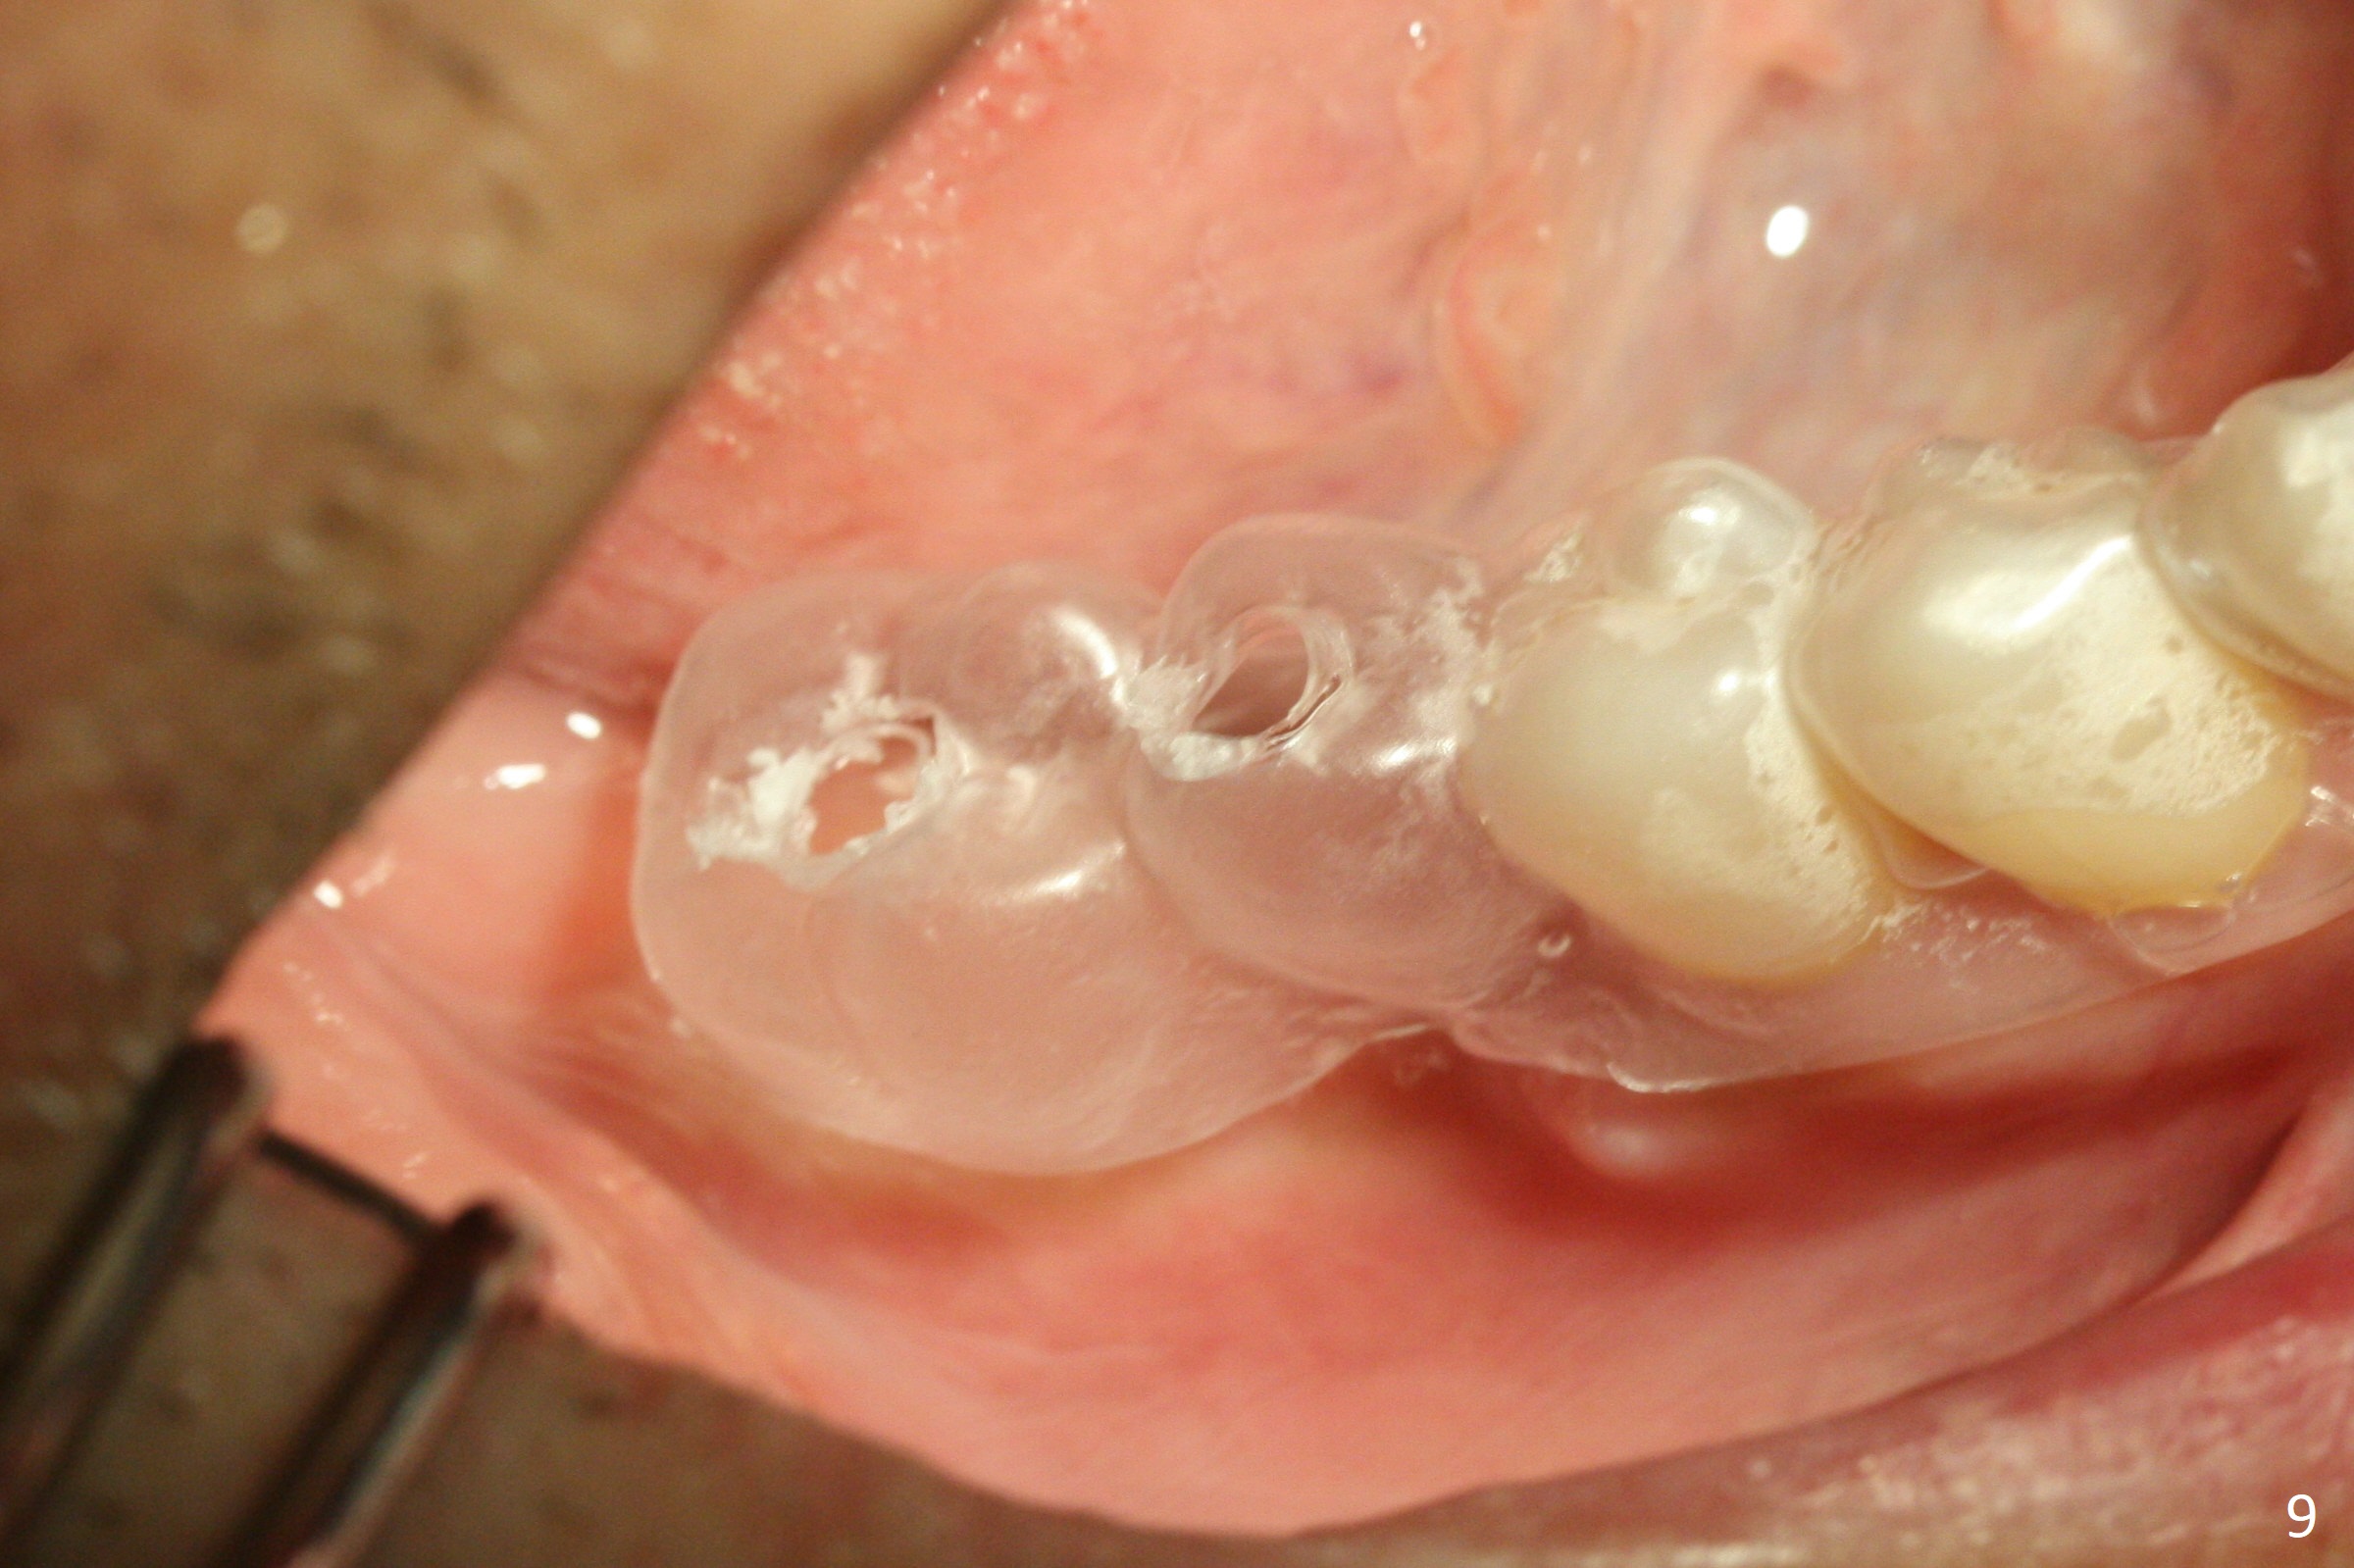

Extraction of the mobile tooth #31 (Fig.1) and debridement of the large socket are not difficult. But making osteotomy buccally does not seem to be easy. It will be difficult to restore. Instead, socket preservation is accomplished by filling the socket with approximately 1.5 cc of Mineralized Cortical/Cancellous allograft until the crest (Fig.2,5). The socket opening is closed by insertion of 4 pieces of PRF membranes (Fig.3) and 4-0 Chromic gut sutures (Fig.4). In the end of surgery, it appears that osteotomy in the center of the socket could be a better approach. Postop re-analysis of CT (Fig.6) and PA (Fig.7) shows that there is 3.9 mm of the native bone to support a 5.5x10 mm implant. Sinus Lift Master Kit should be used with 2 mm initial drill and 2.8 and 3.6 mm round drills with 4 mm stopper.

The socket heals 3 months postop (Fig.8,11). There is vertical loss of the ridge at #31 (Fig.9,10). The implant placed at #31 will be shorter than that at #30 (Fig.12). The patient will return for implant placement 4 months postop.